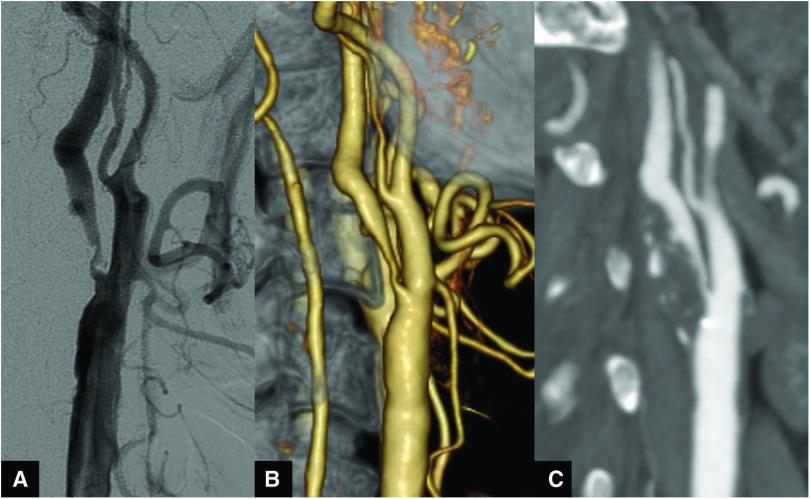

An 80-year-old man underwent carotid artery stenting (CAS) with an open-cell stent to treat asymptomatic right internal carotid artery (ICA) stenosis. Type III stent fracture occurred during CAS. Six months later, in-stent stenosis progressed on DSA. Repeat CAS with a closed-cell stent was performed. CT showed expansion of the narrowed lumen. The patient remained stroke-free and carotid artery restenosis did not occur for 3 years postoperatively.

一名80岁男性接受了使用开放式支架的颈动脉支架置入术(CAS),以治疗无症状的右侧颈内动脉(ICA)狭窄。在CAS过程中发生了III型支架断裂。6个月后,数字减影血管造影(DSA)显示支架内狭窄进展。遂使用闭合式支架重复进行CAS。CT显示狭窄管腔扩张。患者术后3年未发生中风且未出现颈动脉再狭窄。